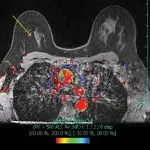

Better Outcomes in Breast Cancer With Complete Response After Neoadjuvant Therapy

Breast cancer pCR after neoadjuvant therapy improves survival and recurrence outcomes, with benefits varying by ...